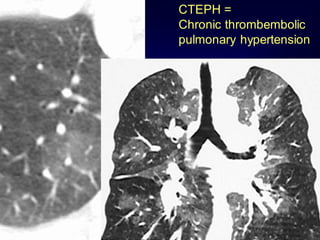

Mosaic Perfusion

Chronic pulmonary embolism

LOOK FOR

Pulmonary hypertension

idiopathic, cardiac disease, pulmonary

disease

CTEPH =

Chronic thrombembolic